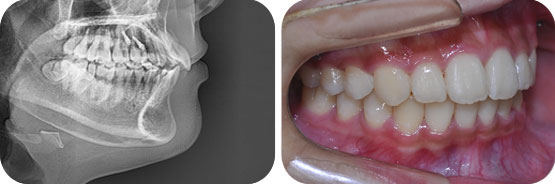

미니스크류를 이용한 돌출입 비 발치 교정

Before

After